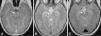

Durante el ingreso presentó paresia del VI par craneal derecho con persistencia de la fluctuación del nivel de conciencia que motivó la realización de TAC craneal con contraste en el que no se observaron alteraciones. Cuarenta y ocho horas más tarde se realizó resonancia magnética (RM) cerebral en la que se observó aumento de intensidad de señal T2 a nivel del tronco del encéfalo, centrada en mesencéfalo con extensión a los pedúnculos cerebrales y al puente, con realce leptomeníngeo y captación puntiforme central en la zona del pedúnculo cerebeloso derecho (fig. 1A y B). Ante la presencia de lesión cerebral de probable origen inflamatorio se completó estudio de autoinmunidad con anticuerpos antinucleares, complemento y anticuerpos anticitoplasma de neutrófilo negativos. Se realizó estudio genético para enfermedades autoinflamatorias hereditarias (fiebre mediterránea familiar, fiebre periódica asociada a déficit de mevalonato kinasa, síndrome TRAPS, síndrome BLAU/sarcoidosis de inicio precoz) sin detectar mutación genética asociada a la enfermedad. El estudio del HLAB51 fue negativo.

A) Axial T1 SPGR: se identifica un aumento de realce en ambos pedúnculos cerebelosos. B) Axial T2 FSE: hiperintensidad de señal T2 en pedúnculo cerebral derecho, con extensión de la alteración de señal hacia la región periacueductal. C) Axial T2 FSE: resolución de las alteraciones postratamiento.

Presentó buena respuesta al tratamiento con mejoría clínica progresiva que permitió el descenso progresivo de los corticoides hasta su suspensión. La RM cerebral de control a los 6 meses de tratamiento no mostraba alteraciones patológicas (fig. 1C). En el momento actual continua tratamiento con azatioprina y colchicina con buena evolución.